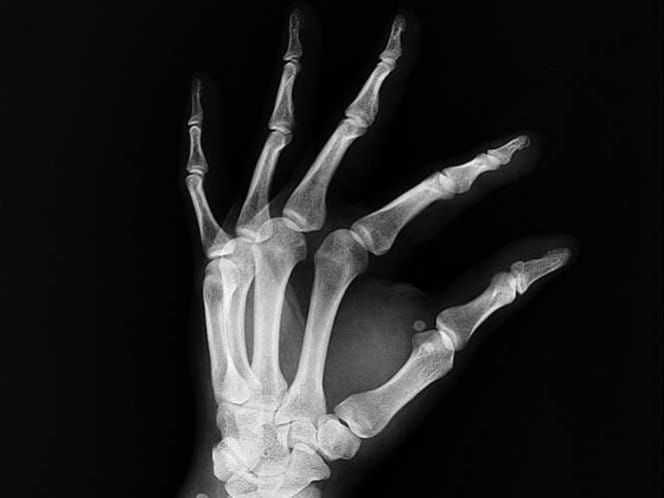

Un grupo de científicos del Instituto Tecnológico de Saltillo (ITS) desarrollaron un material biocerámico celular de baja densidad base sílice para reconstruir o sustituir tejido óseo.

El material es una especie de aerogel con partículas de wollastonita, mineral que se emplea como precursor de bioactividad, explicó la investigadora, Perla Reséndiz Hernández.

“Aquí se obtuvieron materiales conocidos como aerogeles, después continuó la investigación para poder incluir un material precursor del desarrollo de una capa de hidroxiapatita, un compuesto más parecido al componente mineral de los huesos”, apuntó.

Como resultado de este proceso, los especialistas adquirieron un material bioactivo que induce una respuesta biológica específica en la interfaz debido a la unión entre el tejido y el material, por medio de una capa de hidroxiapatita carbonatada.

Dichos componentes se sometieron a pruebas de bioactividad mediante su hundimiento en un fluido fisiológico simulado de concentraciones iónicas similares al plasma sanguíneo humano, a fin de caracterizar su estructura y morfología.

“Se han hecho pruebas de bioactividad, en las cuales ha respondido satisfactoriamente este material a los estudios fisiológicos, esta es la primera etapa para considerarlo un material bioactivo o un material que pueda utilizarse como prótesis en el cuerpo humano”, indicó la investigadora.

En tanto, el doctor Mario Rodríguez Reyes, profesor investigador del Departamento de Metal Mecánica y de la División de Estudios de Posgrado e Investigación del ITS, señaló que todavía faltan más pruebas antes de implantarlo para generar hueso en humanos.

Dicho estudio es parte de un megaproyecto del Instituto en el ámbito de materiales cerámicos celulares, en particular, para aplicaciones biomédicas con el diseño de materiales cerámicos porosos avanzados para la regeneración de tejido óseo.